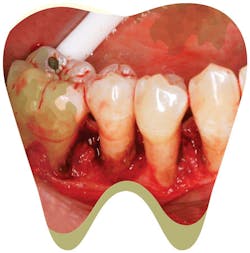

When describing calculus attachment to my patients, I like to use the analogy that the calculus attaches to the tooth like a barnacle attaches to a boat. Barnacles produce cement that is released through the tips of their antennules to attach themselves (Grunbaum, 2010). Calculus attaches by mechanically interlocking to the crystals of the tooth, using the acquired pellicle (Roberts-Harry EA, 2000 ;28). Burnished calculus is a subgingival deposit that has had its outermost layer shaved off - but not fully removed - so that the surface is smooth yet still attached to the tooth surface, contributing to disease (Pattison, 2011). When clinicians do not recognize or remove burnished calculus, they are practicing supervised neglect. One wouldn’t “plane away” a barnacle off a boat, nor should you “shave away” calculus from a tooth; in either scenario, you will leave the source of the irritant.

These areas of burnished deposits will contribute to persistent gingival inflammation and bleeding, in addition to providing a constant food source for more bacteria. This vicious cycle will continue until you completely remove all calculus. We set our patients up for failure when, every six months, we tell them to brush and floss to reduce recurrent bleeding while we leave burnished deposits subgingivally.

Recognizing burnished calculus can be challenging, even for the skilled clinician. Isolated areas of tissue color change, slight inflammation, or bleeding upon probing in a patient who effectively brushes and flosses regularly may be signs of areas where burnished calculus is present. These areas will not heal until the irritant is removed. Change the way you examine your patient to determine if burnished deposits are present.